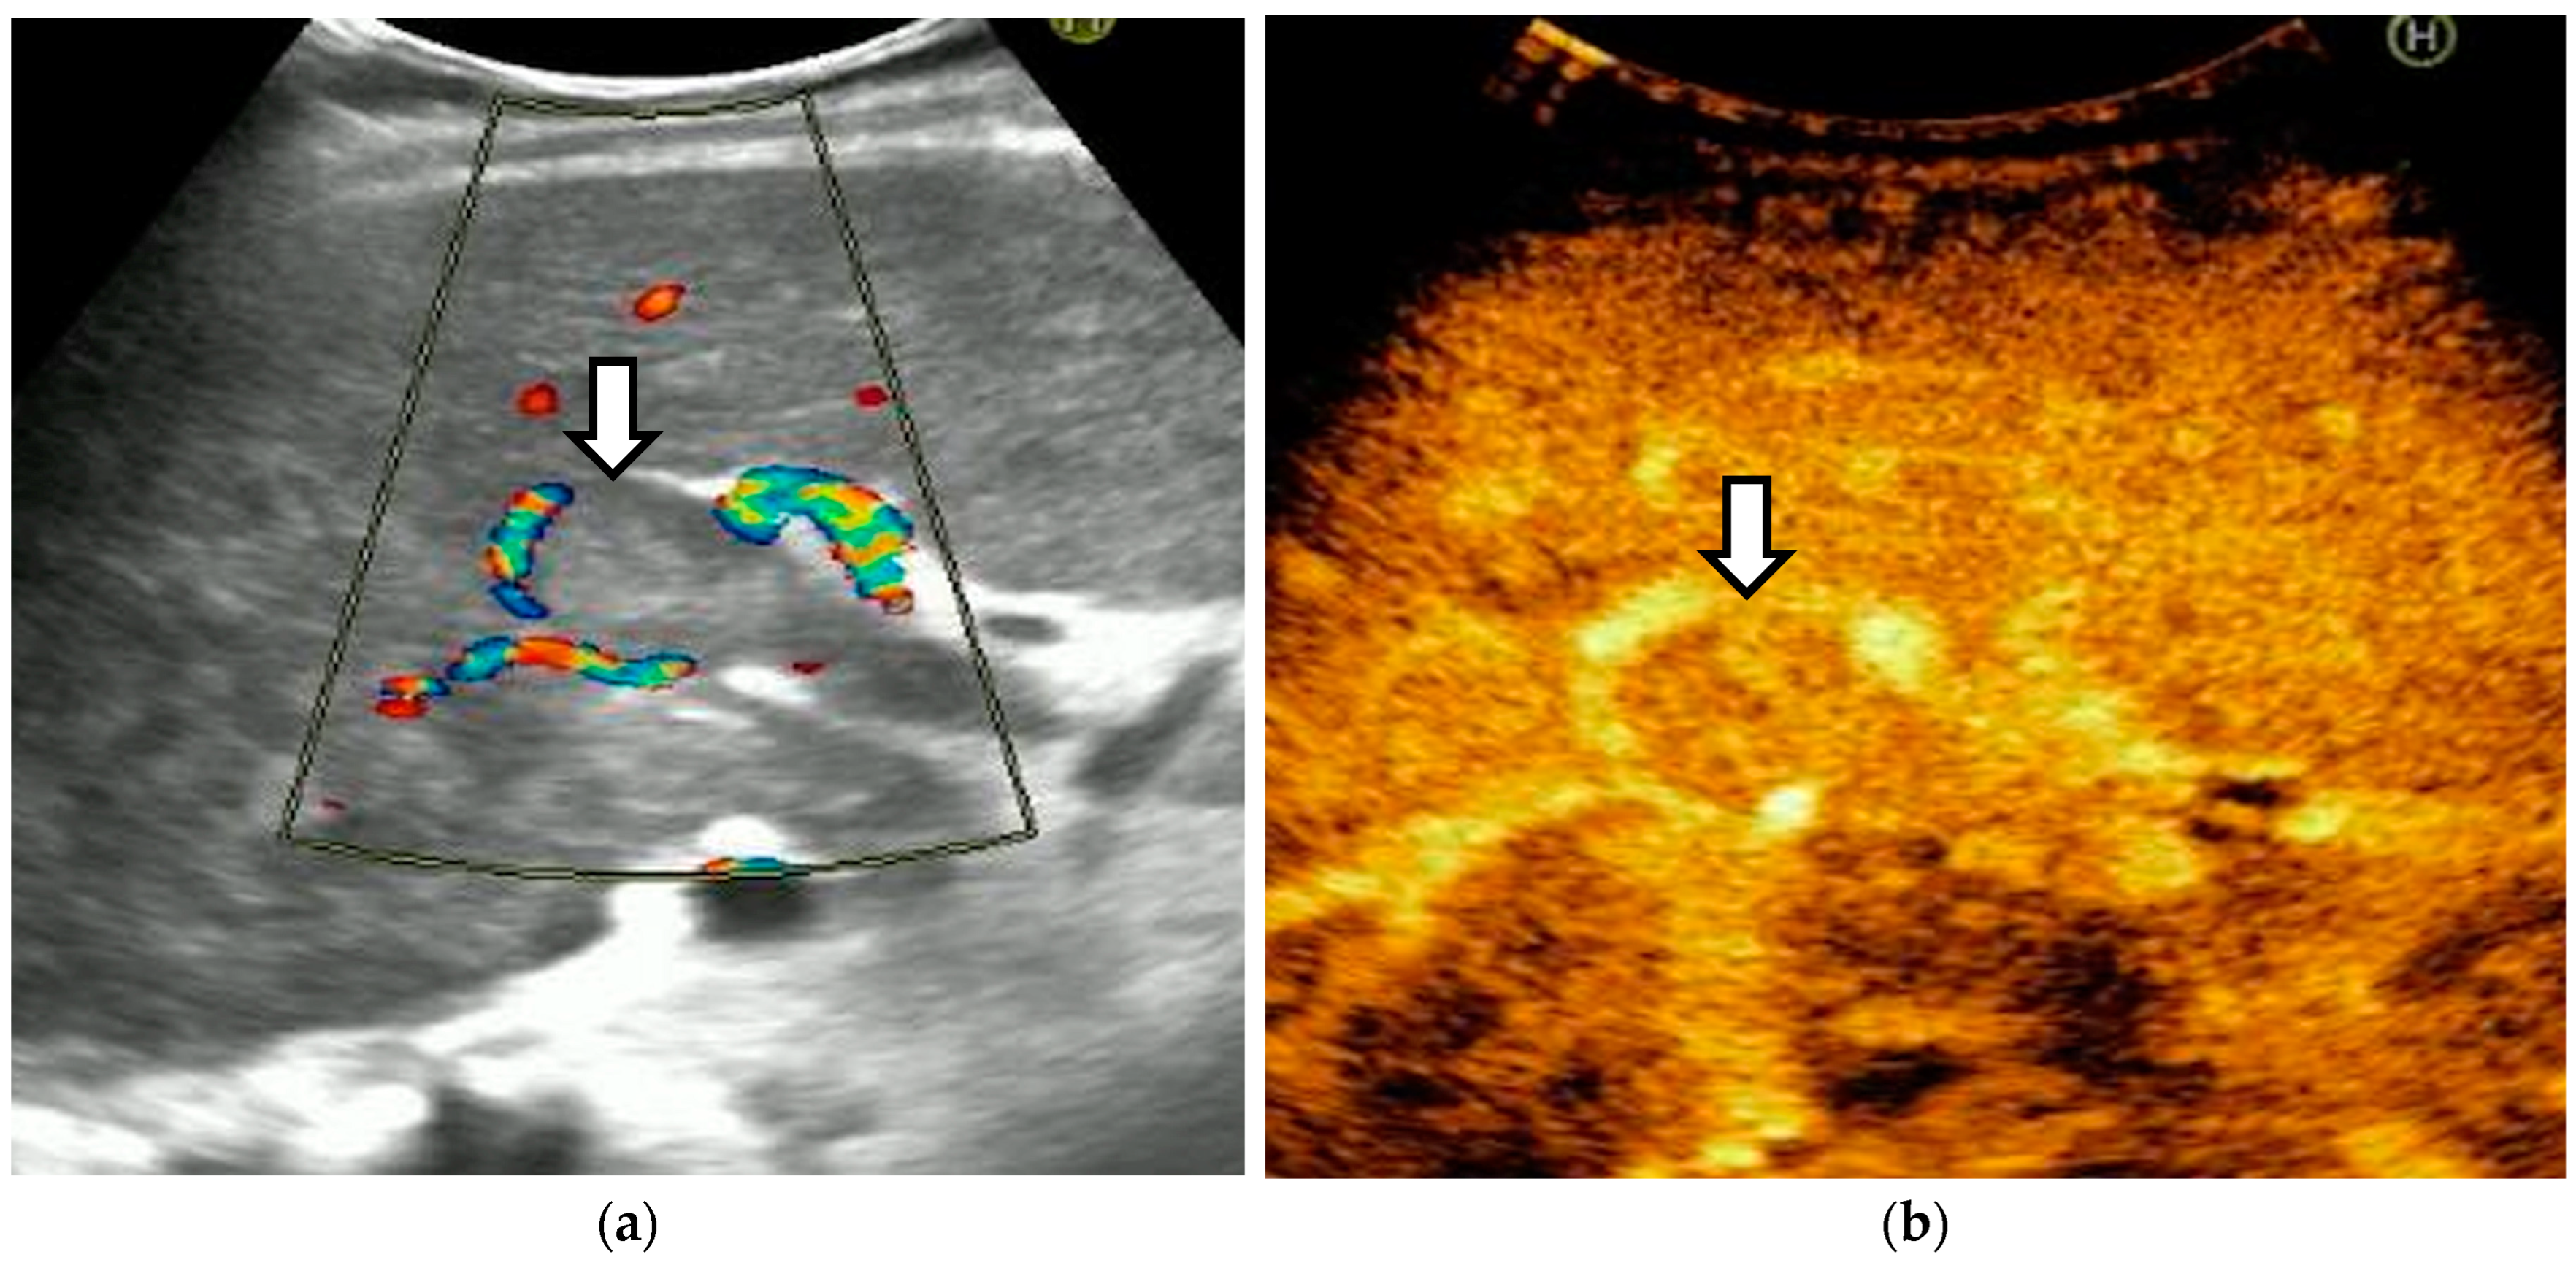

The diagnosis of PVT and PC is made by imaging procedures (transabdominal ultrasound with a Doppler or contrast-enhancing computed tomography scan, magnetic resonance imaging, or angiography in the case of therapeutic intended procedures) [1,3,12,13,14,21,29]. Transabdominal ultrasound is a reliable procedure in 60–100% of cases, with an anechoic aspect in recent cases (requiring Doppler examination or CEUS) and a hypoechoic or hyperechoic aspect in chronic cases [22,29]. Doppler examination may show an anechoic or hypoechoic thrombus and a slower (<15 cm/sec) or absent portal blood flow, and is considered the gold standard (color Doppler) for the diagnosis of PC [1], with a sensitivity and specificity of 95% (Figure 1 and Figure 2) [22]. CEUS can help the diagnosis of benign or malignant PVT, can characterize associated focal liver lesions [30], allows a better characterization of PVT [31], and also permits better detection of PC—Figure 3 and Figure 4 [32]. CT scan and MRI (Figure 5 and Figure 6) are more accurate for the evaluation of liver causes (HCC, abscesses, and other tumors) or other local causes (pancreatitis, diverticulitis, and appendicitis), and for complications (bowel infarction or perforation), and may show permeability of the portal venous system and the flow direction [1,22]. Malignant PVT has intra-thrombus arterial signals on CT, MRI, and/or CEUS, with portal vein diameter frequently 23 mm or above, and with the presence of the tumor at imaging examination (Figure 4 and Figure 6) [21].

Figure 2.

Portal cavernomatous transformation. (a) Portal vein cannot be identified; instead, meandering venous branches are visible in the porta hepatis, indicating portal vein thrombosis and consequent cavernous transformation. (b) Power Doppler ultrasonography identifies flow within the vessels.

Transabdominal ultrasound with Doppler protocol (Figure 1a,b and Figure 2a,b), CT scan (Figure 3a,b), and MRI (Figure 4a,b) were used for the diagnosis in 88.9, 75.1, and 15% of cases, respectively. CEUS was used for the diagnosis in 49 cases (25.9%) but in only 29 cases was it used for the evaluation of the thrombus, and in two cases for cavernoma diagnosis (Figure 5a,b and Figure 6a,b).